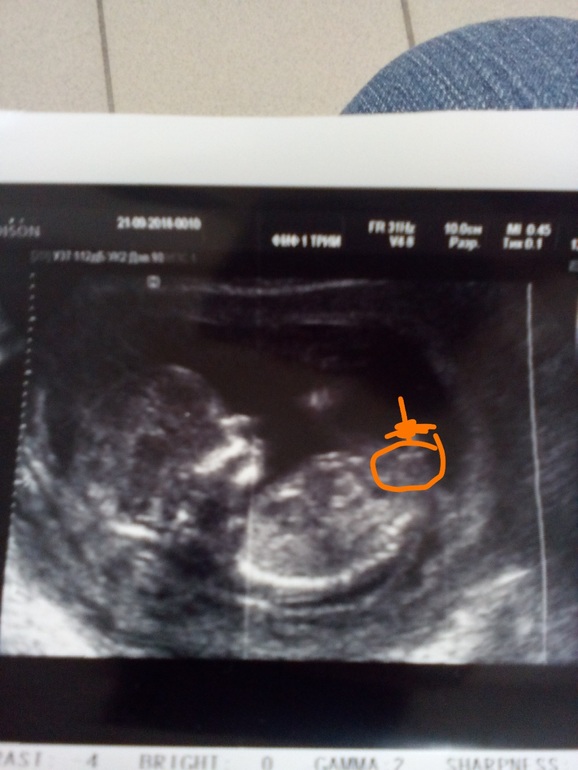

Пол малышаДевочки,вчера прошла первый скрининг,врач пол не стала предполагать,дала лишь. Фото,,,сказала все равно сейчас не точно,,, я вчера загрузила,и многие сказали сто похож малыш на мальчика!!! Вы не подумайте,я и мальчику буду рада и буду любить, но все же мечтают о доче,ведь сынок уже есть у нас любимый!!! Посмотрите ещё фото- одно оригинал,а второе я отредактировала, и посетила где ( как мне на самом деле кажется) тот самый бугорок! То ,что на первом фото( по чему все ставят на мальчика)- мне кажется это ножка, просто с такого ракурса))) если бы все было так вероятно, то арас бы мне сказала ( я думаю)!!! Фото под кат

Так не бугорок смотрят на таком сроке, а угол острый или тупой, и строго в определенном ракурсе

Похож на наш,но как написали ниже должен быть строго определенный ракурс,поэтому сложно сказать

Вот моя доча в 11.4 недели и тоже так же торчит. Эти бугорки надо смотреть только в средне сегитальном срезе, вроде правильно написала.